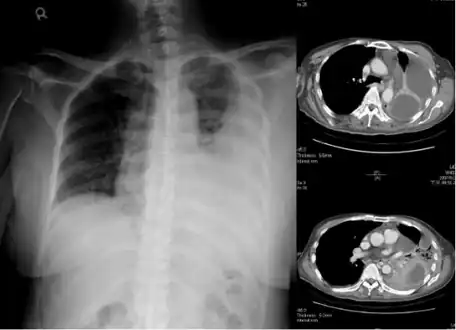

Empyema -

Empyema with abscess